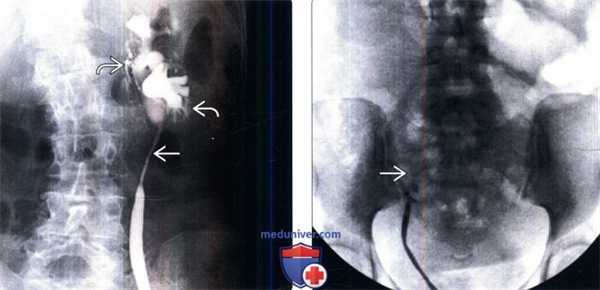

(Слева) Ретроградная пиелография: стриктура длинного сегмента проксимального отдела мочеточника с расширением чашечек. Обратите внимание на интравазацию контраста указывающую на перерастяжение собирательной системы под давлением. Эта стриктура образовалась после хирургической экстракции камня из мочеточника.

(Справа) Ретроградная пиелография: полная обструкция правого мочеточника на уровне входа в таз. Эта стриктура является следствием повреждения мочеточника при гинекологической операции. Такие признаки обнаружены на антеградной пиелографии (изображение отсутствует).

(Слева) Ретроградная пиелография: медиальное отклонение обоих мочеточников и их частичная обструкция. Данные визуализации характерны для забрюшинного фиброза. На КТ с контрастированием был подтвержден данный диагноз, поскольку был обнаружен ореол из ткани, окружающей аорту, нижнюю полую вену и дистальные отделы мочеточников.

(Справа) Ретроградная пиелография: эксцентричный дефект наполнения и стриктура дистального отдела мочеточника. Оба образования имеют неровную гладкую поверхность. Эти данные говорят о наличии стриктуры, вызванной злокачественным новообразованием, в данном случае - переходноклеточным раком.